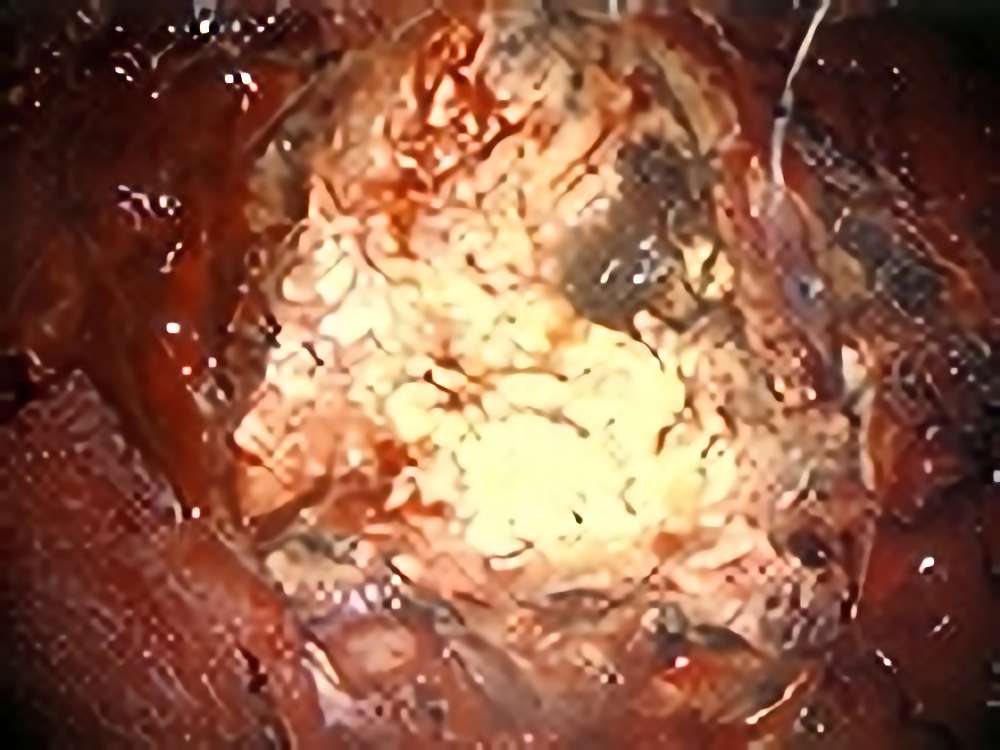

術中写真

摘出 前